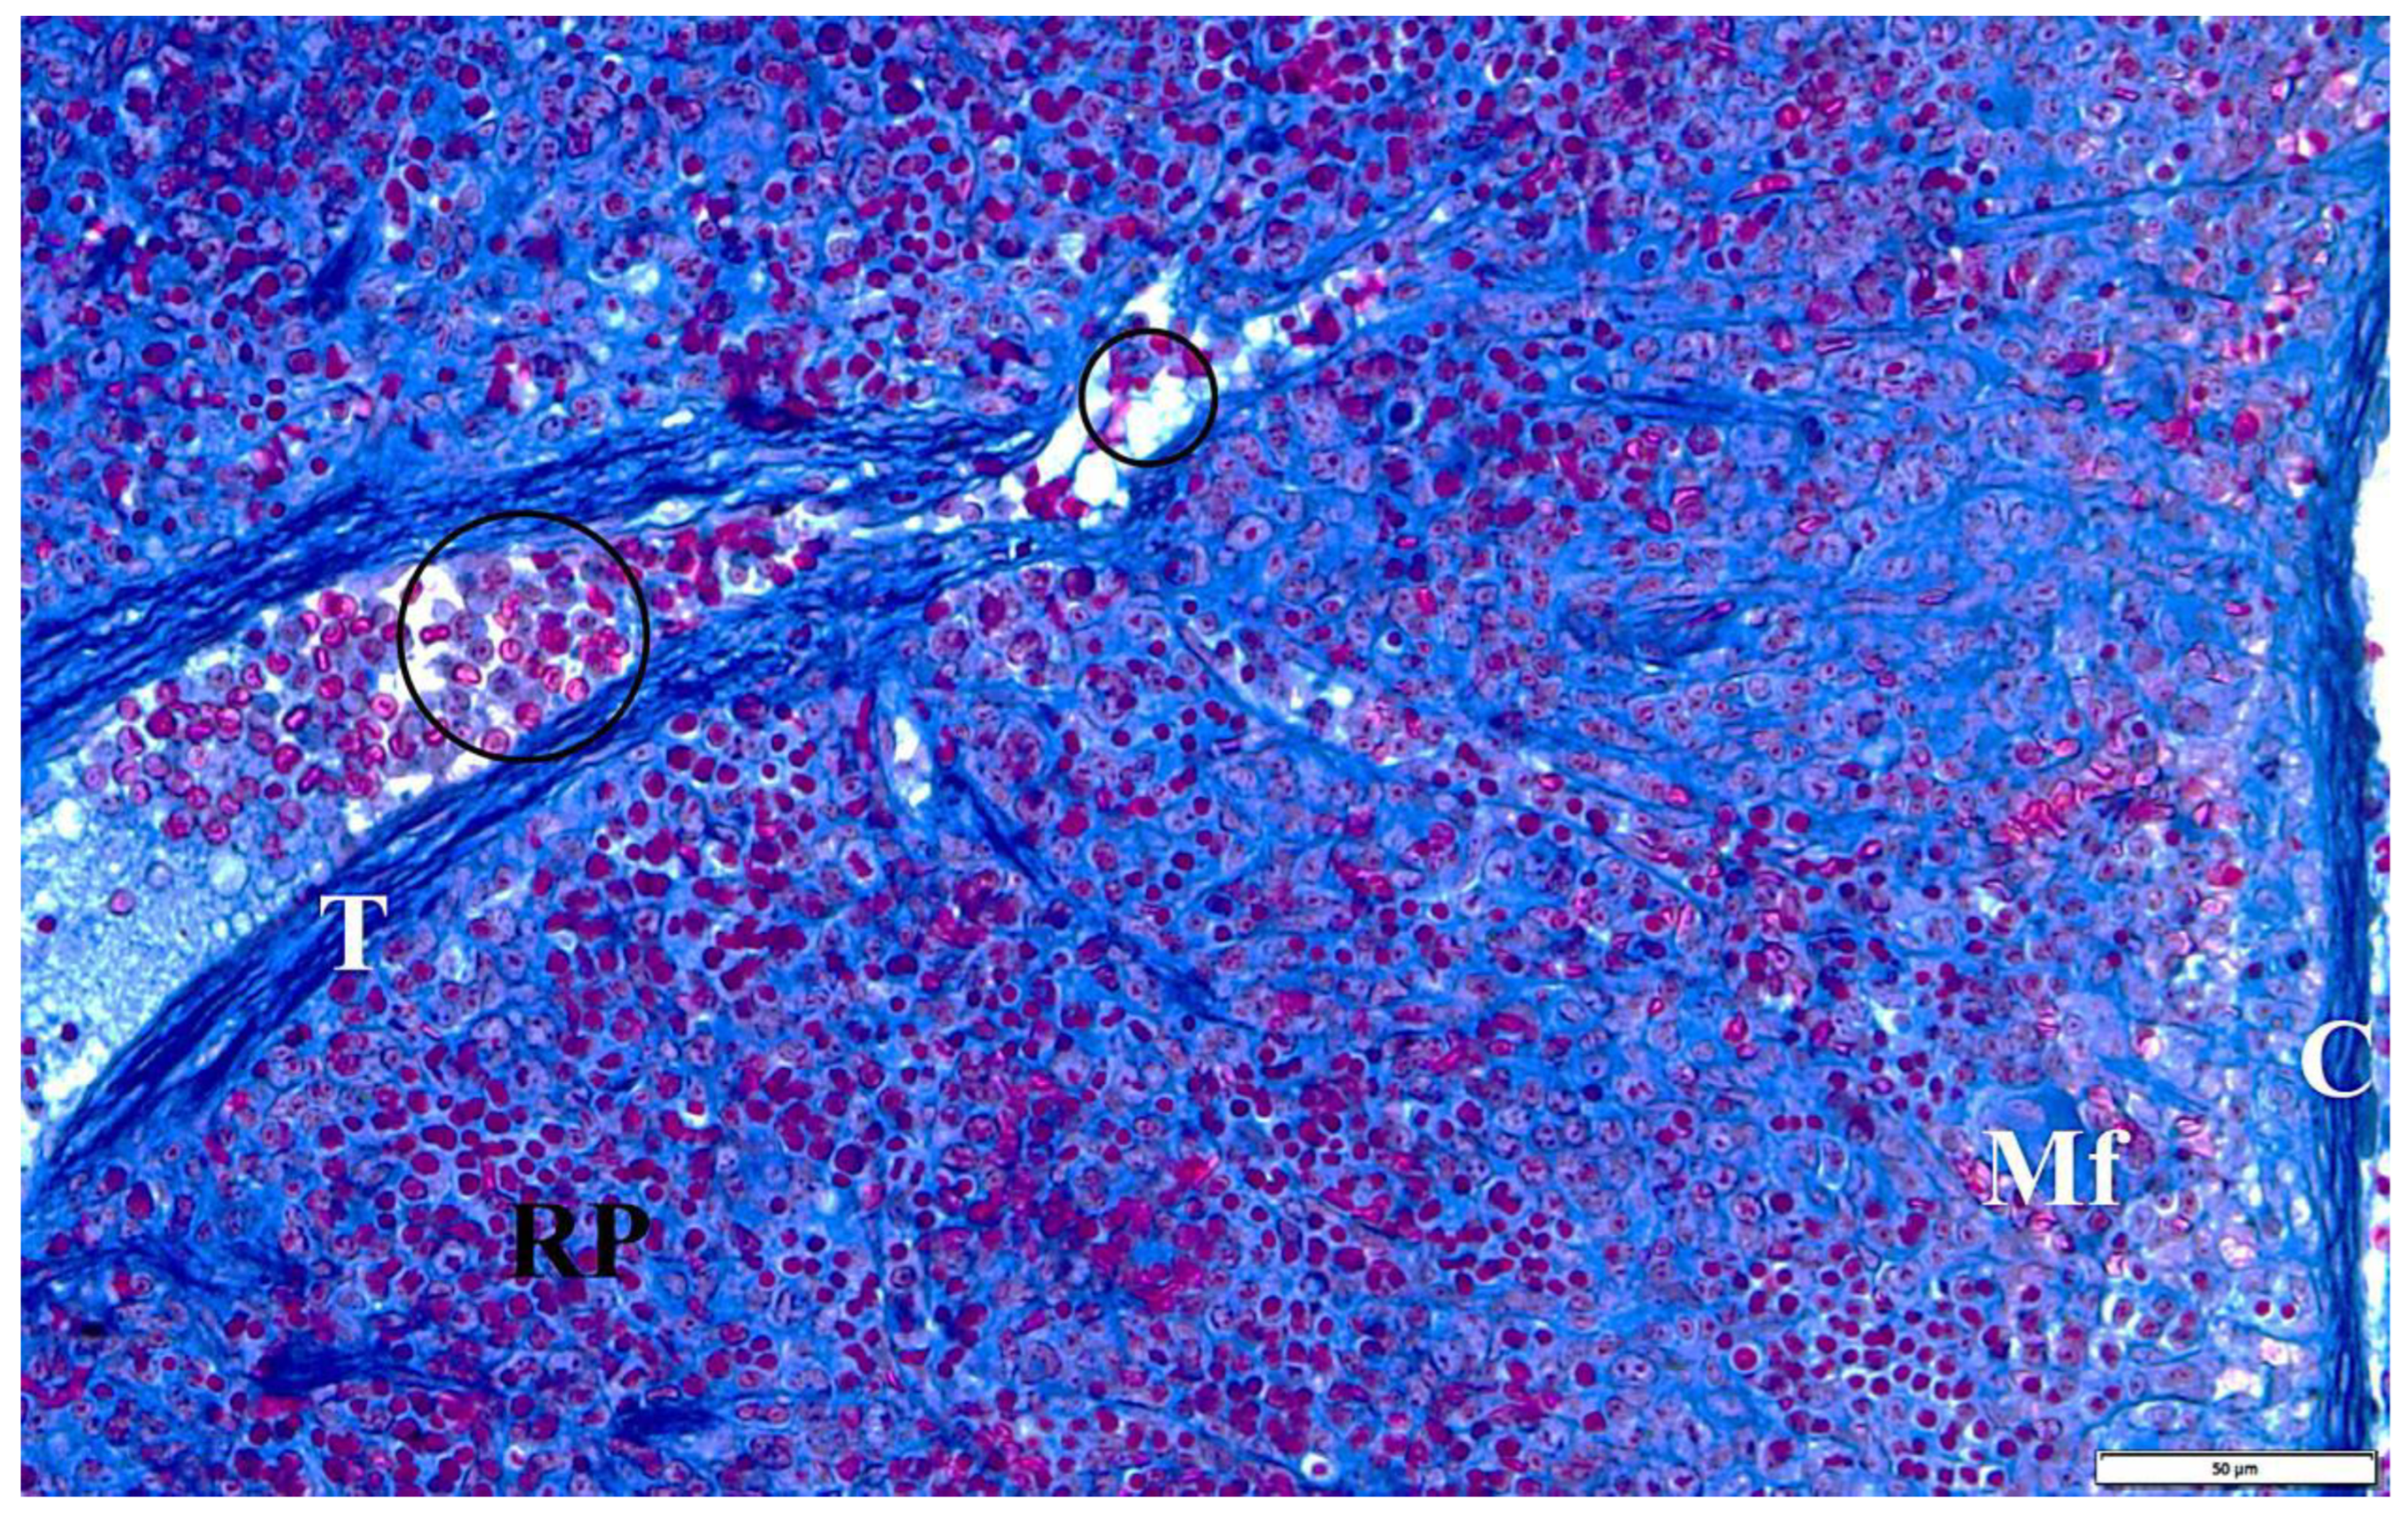

Figure 9.

The spleen of a rat with transplacental infection with B. microti 3 weeks after birth. C—fibrous capsule, Mf—macrophage, RP—red pulp, T—trabecula with a trabecular vessel, circular markings—longitudinal sections through trabecular vessels with multicolored erythrocytes and congestive changes.

In the presented studies, in the histological structure of the spleen of intrauterine infected rats with B. microti, no clear deviations from the normal architecture of the organ were observed, appropriate to the young age of the observed individuals. Both white and red pulp were visible. However, the line between them was blurred (Figure 8). The lymphoid follicles were irregular in shape and the marginal layer was barely perceptible. The fibrous capsule of the spleen of rats under physiological conditions is characterized by a small amount of connective tissue. In the observed preparations of spleen sections taken from rats with congenital babesiosis, a small amount of it was visible with the presence of mesothelial cells covering its surface. The connective tissue capsule detached from the parenchyma of the organ in places, creating fissured spaces. These dissections indicate degenerative changes, possibly associated with edema. The trabeculae extending from the splenic capsule were visible and contained vessels with fibrin-precipitated hyperemia and numerous blood cells adhering to the endothelial wall (Figure 9). In addition, a characteristic feature was the differentiation of erythrocytes.